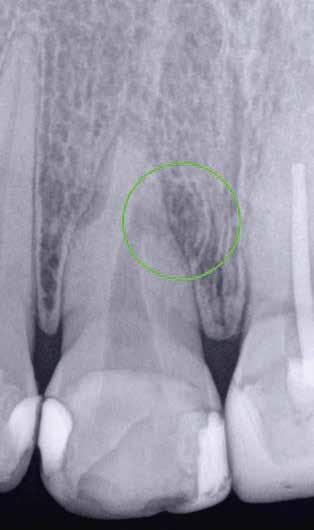

1. a–g. ábrák: A direkt pulpasapkázás lépései. Kiindulási bitewing-felvétel: A meglévő restaurátum közel helyezkedett el a pulpakamrához (a). Kiindulási periapicalis felvétel: Nincs periapicalis elváltozás fennállására utaló jel (b). A pulpaexpozíció (c). A vérzéscsillapítás céljából 20 másodpercen keresztül steril vattagombóccal történő kompressziót követően látható pulpaseb (d). A pulpasapkázás céljából behelyezett anyag, a széli részek tisztázása előtt készült felvétel (e). A röntgenárnyékot nem adó ideiglenes tömés behelyezése után készült felvétel (f). Az első ülés végén a röntgenárnyékot nem adó ideiglenes töméssel ellátott fogról készített röntgenfelvétel (g).

2. ábra: A hat hónapos kontroll alkalmával készített röntgenfelvételen vastag dentinhíd látható a pulpasapkázó anyag alatt.

3. ábra: A hároméves kontroll alkalmával készített röntgenfelvételen megfigyelhető a restaurátum pontos illeszkedése.

A kezelést követően a beteg tünetmentes volt. A kérdéses fog a kontrollvizsgálatok során végzett szenzibilitástesztekre fiziológiás reakciókat adott. A hat hónapos kontroll alkalmával készített röntgenfelvételen a sérülésnek megfelelően széles dentinhidat észleltünk (2. ábra). A restaurátum a hároméves kontroll során is megfelelőnek bizonyult (3. ábra)